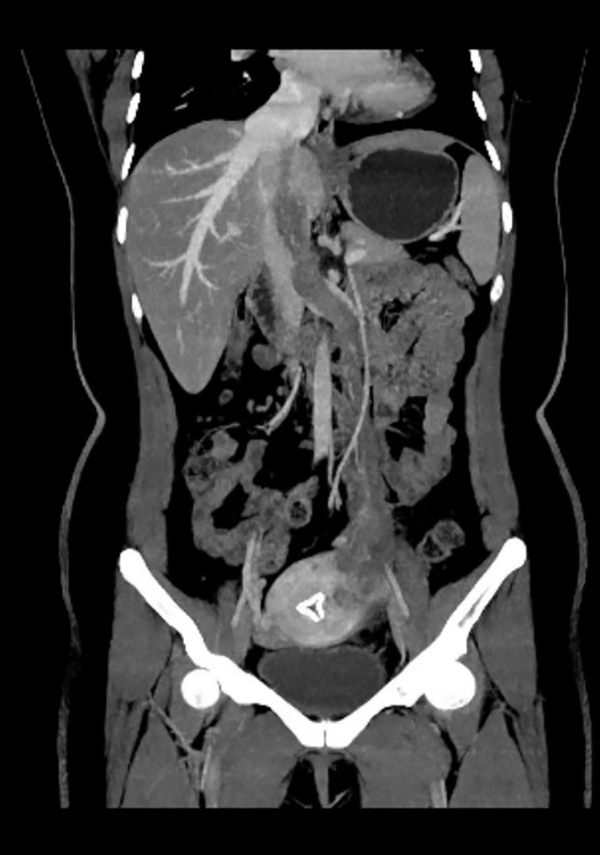

今年39岁的王女士觉得自己活动后稍有憋喘,开始还以为是变胖了,也就没在意,后来活动后憋喘的症状逐渐加重,这才到当地医院就诊。当地医院心脏彩超提示患者右心房占位,考虑黏液瘤,王女士慕名来到省立医院东院心外科。术前心脏彩超检查提示右房占位与下腔静脉关系不清,主管医师张杰敏锐的察觉到患者的肿瘤可能没有预想的那么简单,于是立即为王女士安排了妇科B超、下腔静脉CTV、肺动脉CTA检查,最终的检查结果验证了张杰医师的判断,王女士心脏里的占位不是一般的粘液瘤,影像学上更考虑血管平滑肌瘤。这是具有恶性生长行为的良性肿瘤,沿左侧子宫静脉,左侧卵巢静脉,左肾静脉近心段走行,如同藤蔓一样由下腔静脉进入右心房,随心跳而往返于右房右室之间。

手术当天,在麻醉手术科团队的保驾护航下,妇产科副主任医师李娜首先成功完整切除患者全子宫双附件,去除了因激素引起肿瘤复发的隐患。随后,普外科主任医师张小桥和血管外科主任医师董典宁逐步沿卵巢静脉向上游离肿瘤。然而肿瘤却异常“狡猾”,术中食道超声提示肿瘤正在随着心跳慢慢的往右室流出道游走,马上要阻塞右室流出道。紧急关头,心外科主任医师訾捷、主治医师张杰立即按照手术预案开胸建立体外循环……经过数小时的艰苦协作,最终,王女士长约30厘米的下腔静脉瘤栓被完整取出。